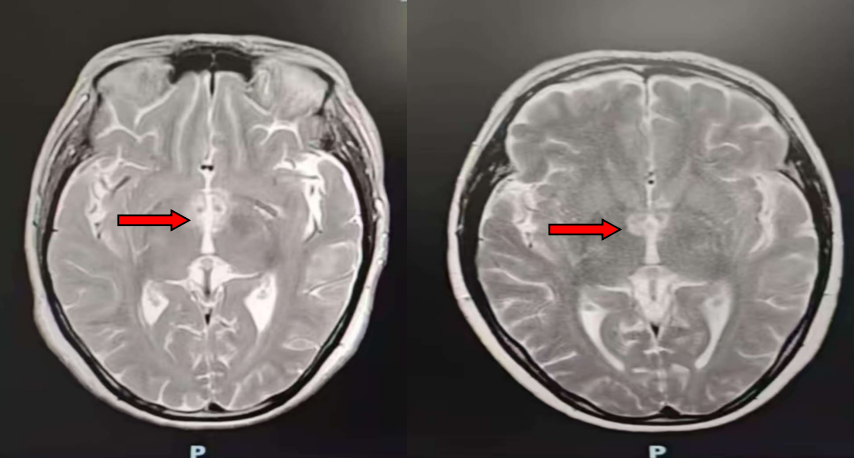

风湿免疫科欧阳楚君副主任接诊后,发现患者自身抗体谱更符合干燥综合征,需鉴别颅内感染与原发病活动,随即安排头颅MRA、腰椎穿刺及脑脊液相关检测。鉴于病情复杂,科室迅速启动多学科协作诊疗(MDT),联合神经内科、呼吸科等多科室专家会诊。结合影像学双侧丘脑及颈髓异常信号、脑脊液AQP4抗体阳性结果,最终明确诊断为“干燥综合征合并视神经脊髓炎”。

△治疗前头颅MR提示双侧丘脑内侧、灰结节脑实质异常信号影

△治疗后双侧丘脑内侧、灰结节脑实质异常信号影减轻